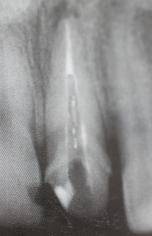

5.有对纤维桩X线阻射性能的要求,这关系到医生在修复时与修复后的检查和诊断…

预备后根管壁上会不同程度的牙胶和封闭剂等残留物,所以桩道预备前后建议X线片辅助检查预备深度等情况,而残留物也会很清晰地显现。